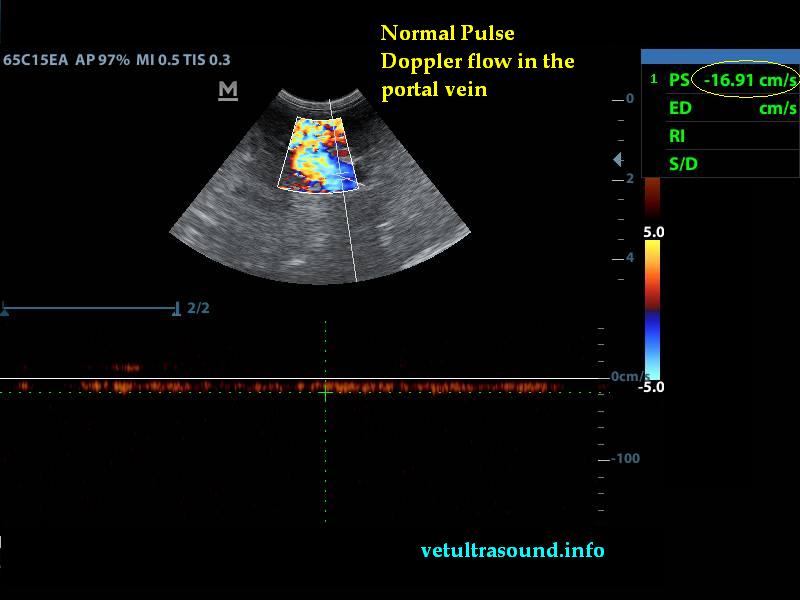

Στον υπέρηχο βρέθηκε ανομοιογένεια του ηπατικού παρεγχύματος, πολυάριθμοι κυστικοί σχηματισμοί οι οποίοι καταλάμβαναν κυρίως τον δεξιό πλάγιο λοβό του οργάνου(pic1&2). Η ροή του αίματος στη πυλαία φλέβα με τη βοήθεια του Pulse Wave Doppler βρέθηκε φυσιολογική(pic3), ενώ σε κλάδο της δεξιάς ηπατικής αρτηρίας ο δείκτης αγγειακής αντίστασης βρέθηκε μειωμένος(normal RI≈ 0.55)(pic4). Στοιχείο που μας δείχνει πως είτε η αγγείωση στη συγκεκριμένη περιοχή είναι νεόπλαστη, είτε λόγω χρόνιας νόσου ο διάμεσος ιστός που περιβάλλει τα αγγεία έχει χάσει την σκληρότητά του. Μικρή ποσότητα ασκιτικού υγρού βρέθηκε ανάμεσα στις εντερικές έλικες. Χωρίς παθολογικά διογκωμένους λεμφαδένες εκτιμήθηκε η κοιλιακή κοιλότητα(pic5). Οι υπόλοιπες δομές ελέγχθηκαν χωρίς παθολογικά ευρήματα.